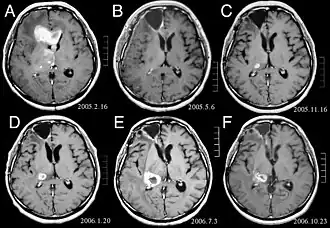

![]() (A) La imagen de RM muestra un tumor en los lóbulos frontales derecho y izquierdo, así como en el tálamo derecho. (B) RM después del tratamiento con resección quirúrgica, radioterapia y quimioterapia. El tumor ha desaparecido por completo, excepto por un ligero realce adyacente al margen quirúrgico. (C) Recurrencia del tumor talámico 9 meses después, a pesar de la quimioterapia de mantenimiento. (D) Crecimiento del tumor talámico dos meses después de la radioterapia estereotáxica. (E) Después de 6 ciclos de quimioterapia con temozolomida, la lesión talámica ha aumentado y el paciente presenta disartria y hemiparesia. (F) Después de 2 ciclos de tratamiento con interferón-beta y temozolomida, el tumor muestra una regresión parcial. | ||